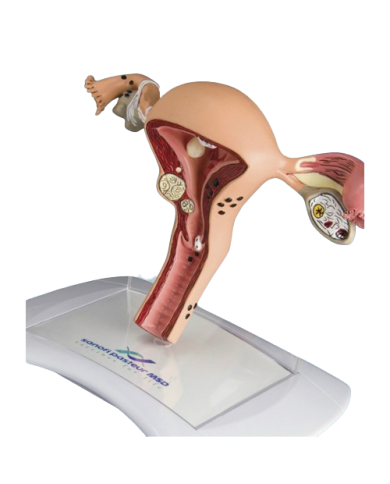

Modello anatomico PER FORNITURE CASE FARMACEUTICHE

Modello anatomico PER FORNITURE CASE FARMACEUTICHE

Modello anatomico PER FORNITURE CASE FARMACEUTICHE

Modello anatomico PER FORNITURE CASE FARMACEUTICHE

Modello anatomico PER FORNITURE CASE FARMACEUTICHE

Modello anatomico PER FORNITURE CASE FARMACEUTICHE

Modello anatomico PER FORNITURE CASE FARMACEUTICHE

Modello anatomico PER FORNITURE CASE FARMACEUTICHE

Modello anatomico PER FORNITURE CASE FARMACEUTICHE

Modello anatomico PER FORNITURE CASE FARMACEUTICHE

Modello anatomico PER FORNITURE CASE FARMACEUTICHE

Modello anatomico PER FORNITURE CASE FARMACEUTICHE

Modello anatomico PER FORNITURE CASE FARMACEUTICHE

Modello anatomico PER FORNITURE CASE FARMACEUTICHE

Modello anatomico PER FORNITURE CASE FARMACEUTICHE

Modello anatomico PER FORNITURE CASE FARMACEUTICHE

Modello anatomico PER FORNITURE CASE FARMACEUTICHE

Modello anatomico PER FORNITURE CASE FARMACEUTICHE

Modello anatomico PER FORNITURE CASE FARMACEUTICHE

Modello anatomico PER FORNITURE CASE FARMACEUTICHE

Modello anatomico PER FORNITURE CASE FARMACEUTICHE

Modello anatomico PER FORNITURE CASE FARMACEUTICHE